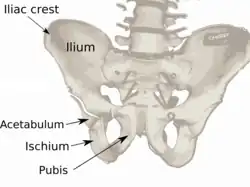

Overview of Ilium as largest bone of the pelvis | |

The crest of the ilium (or iliac crest) is the superior border of the wing of ilium and the superiolateral margin of the greater pelvis.

The iliac crest stretches posteriorly from the anterior superior iliac spine (ASIS) to the posterior superior iliac spine (PSIS). Behind the ASIS, it divides into an outer and inner lip separated by the intermediate zone. The outer lip bulges laterally into the iliac tubercle.[1] Palpable in its entire length, the crest is convex superiorly but is sinuously curved, being concave inward in front, concave outward behind.[2]